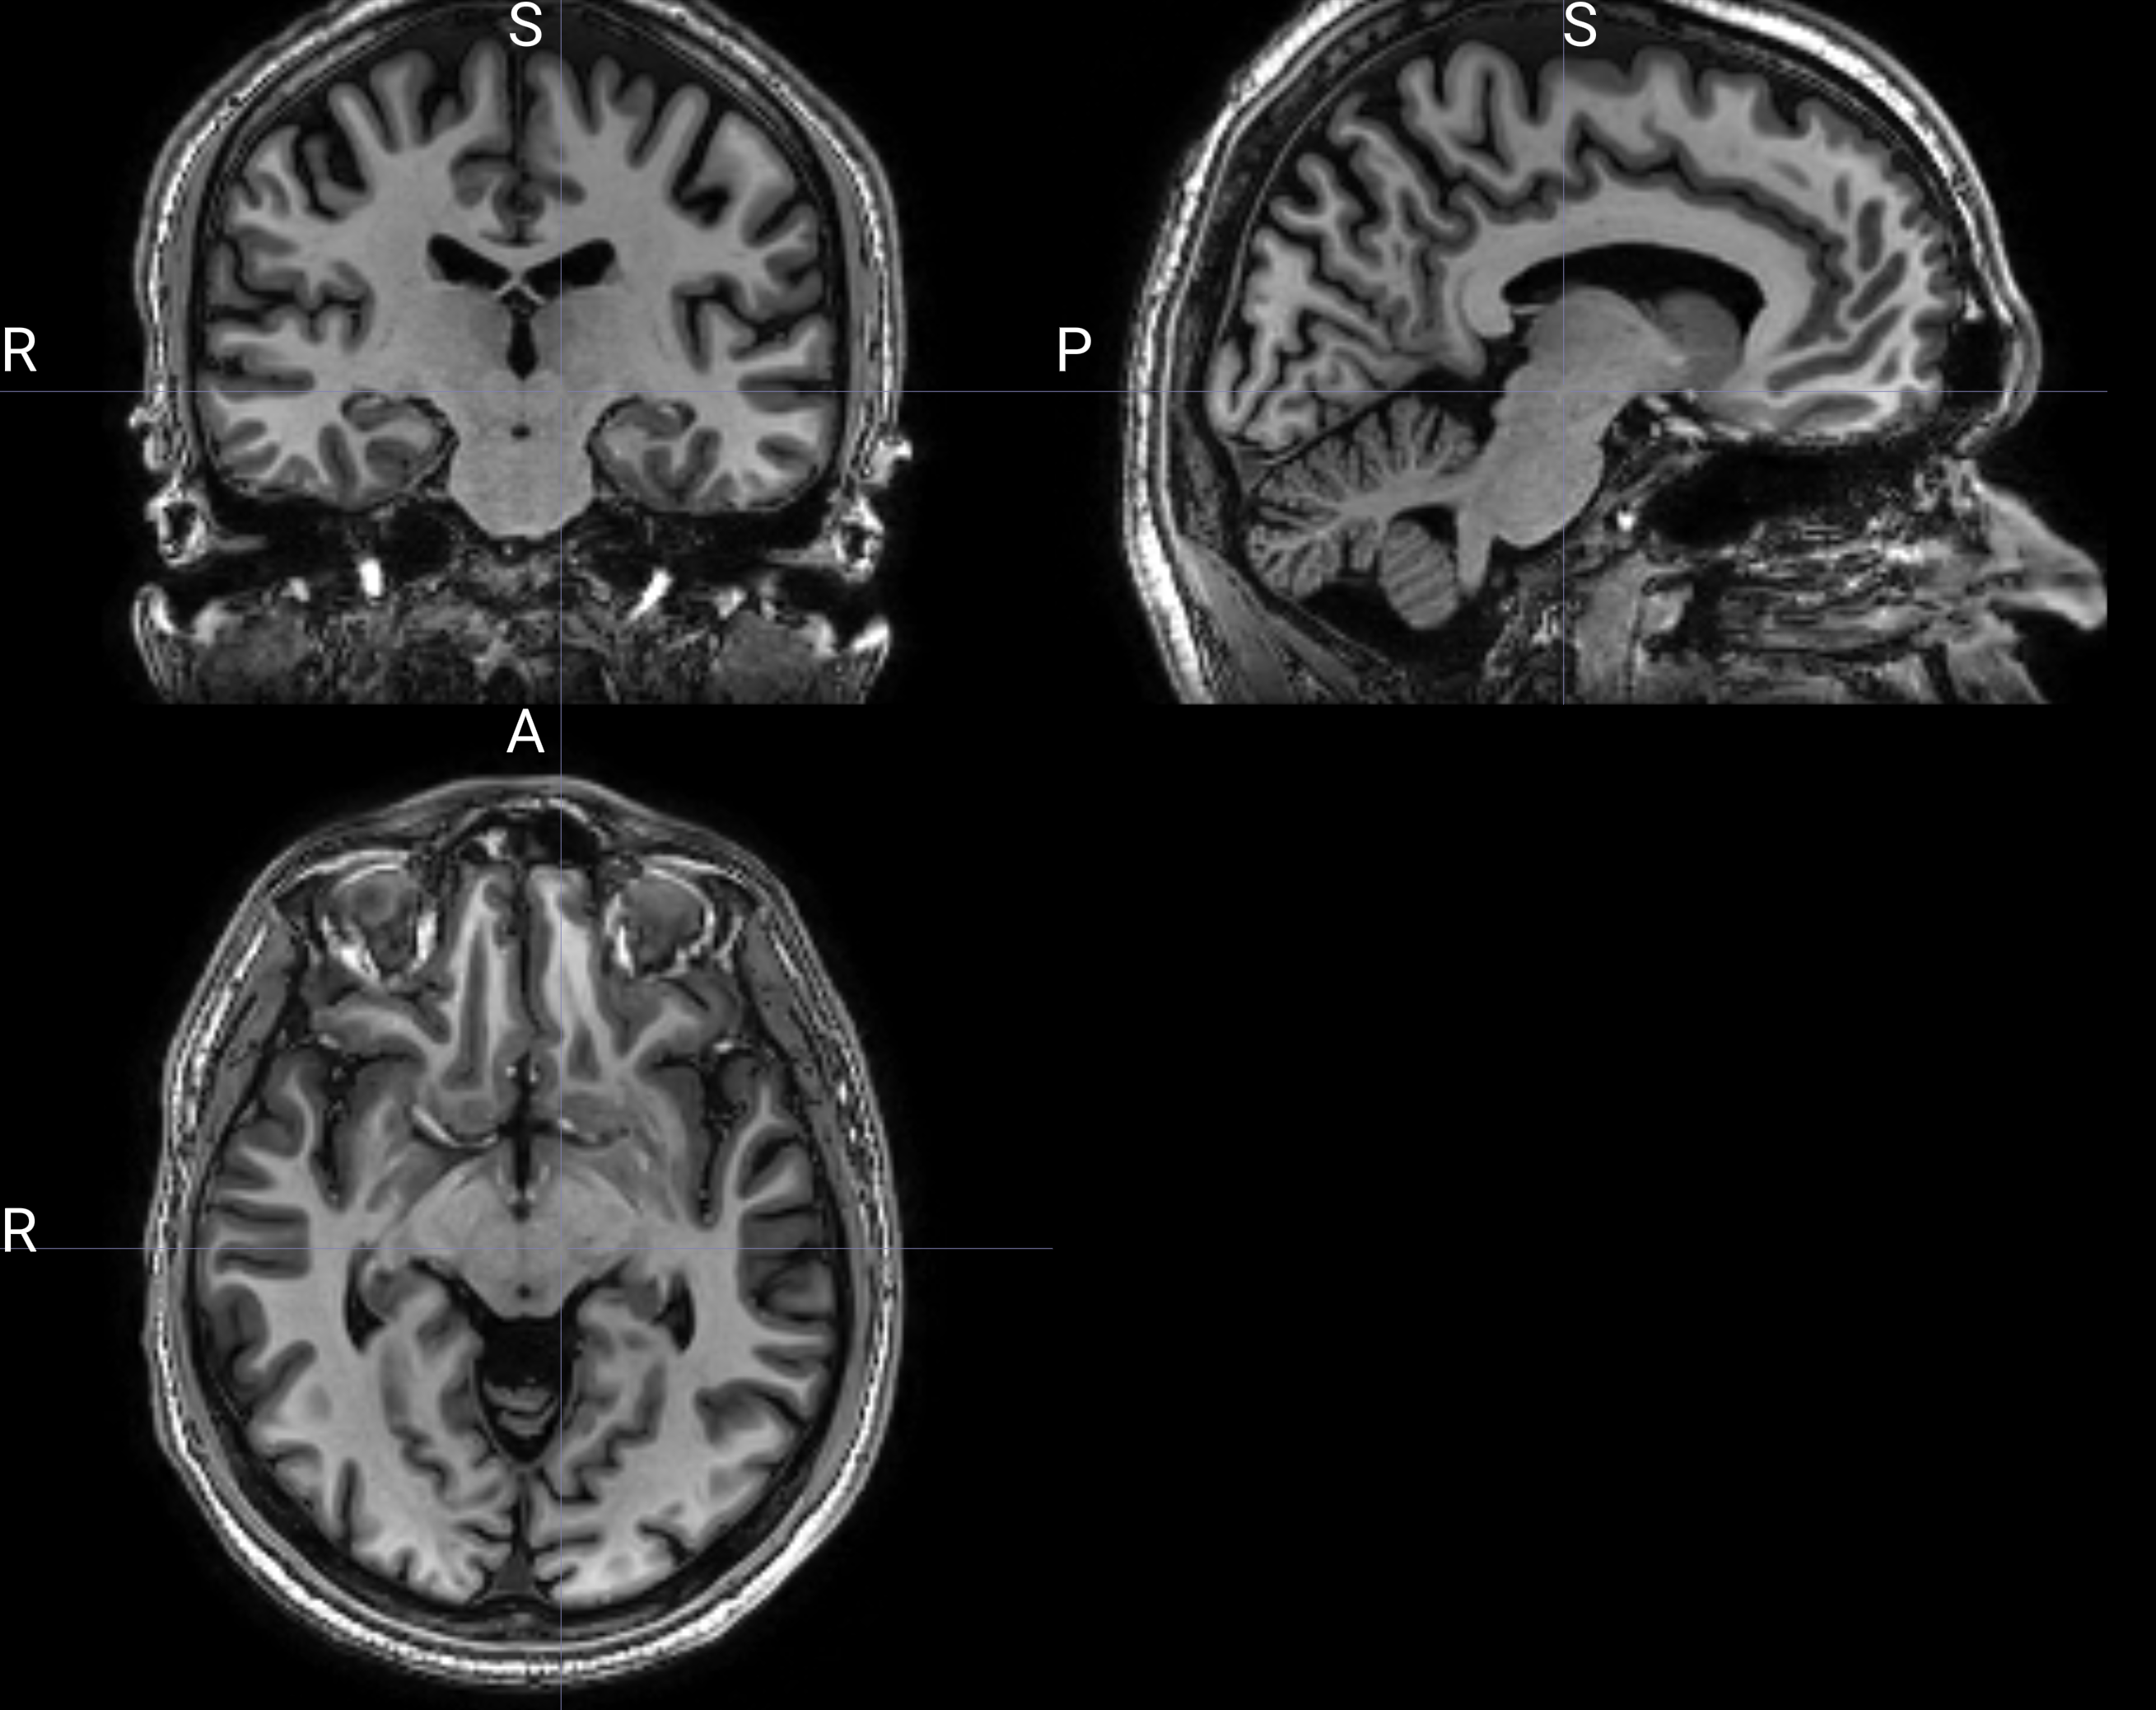

My research program centers on crafting machine learning models for the automatic detection, differential diagnosis, and longitudinal tracking of Primary Progressive Aphasia (PPA), Alzheimer’s disease, and Mild Cognitive Impairment. By utilizing multimodal data—including spoken language, structural and functional MRI, and neurophysiological assessments—we aim to transform early clinical diagnostics.